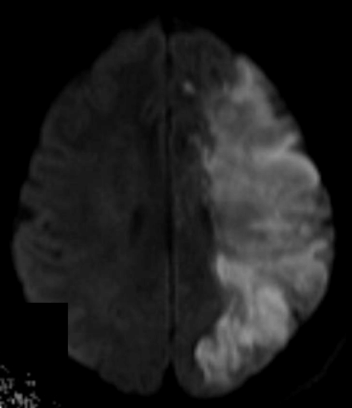

¿En qué fase nos sirve la RM y qué secuencia se usa?

Se usa la secuencia de difusión en la fase aguda para ver el infarto

Q

A

La hiperintensa